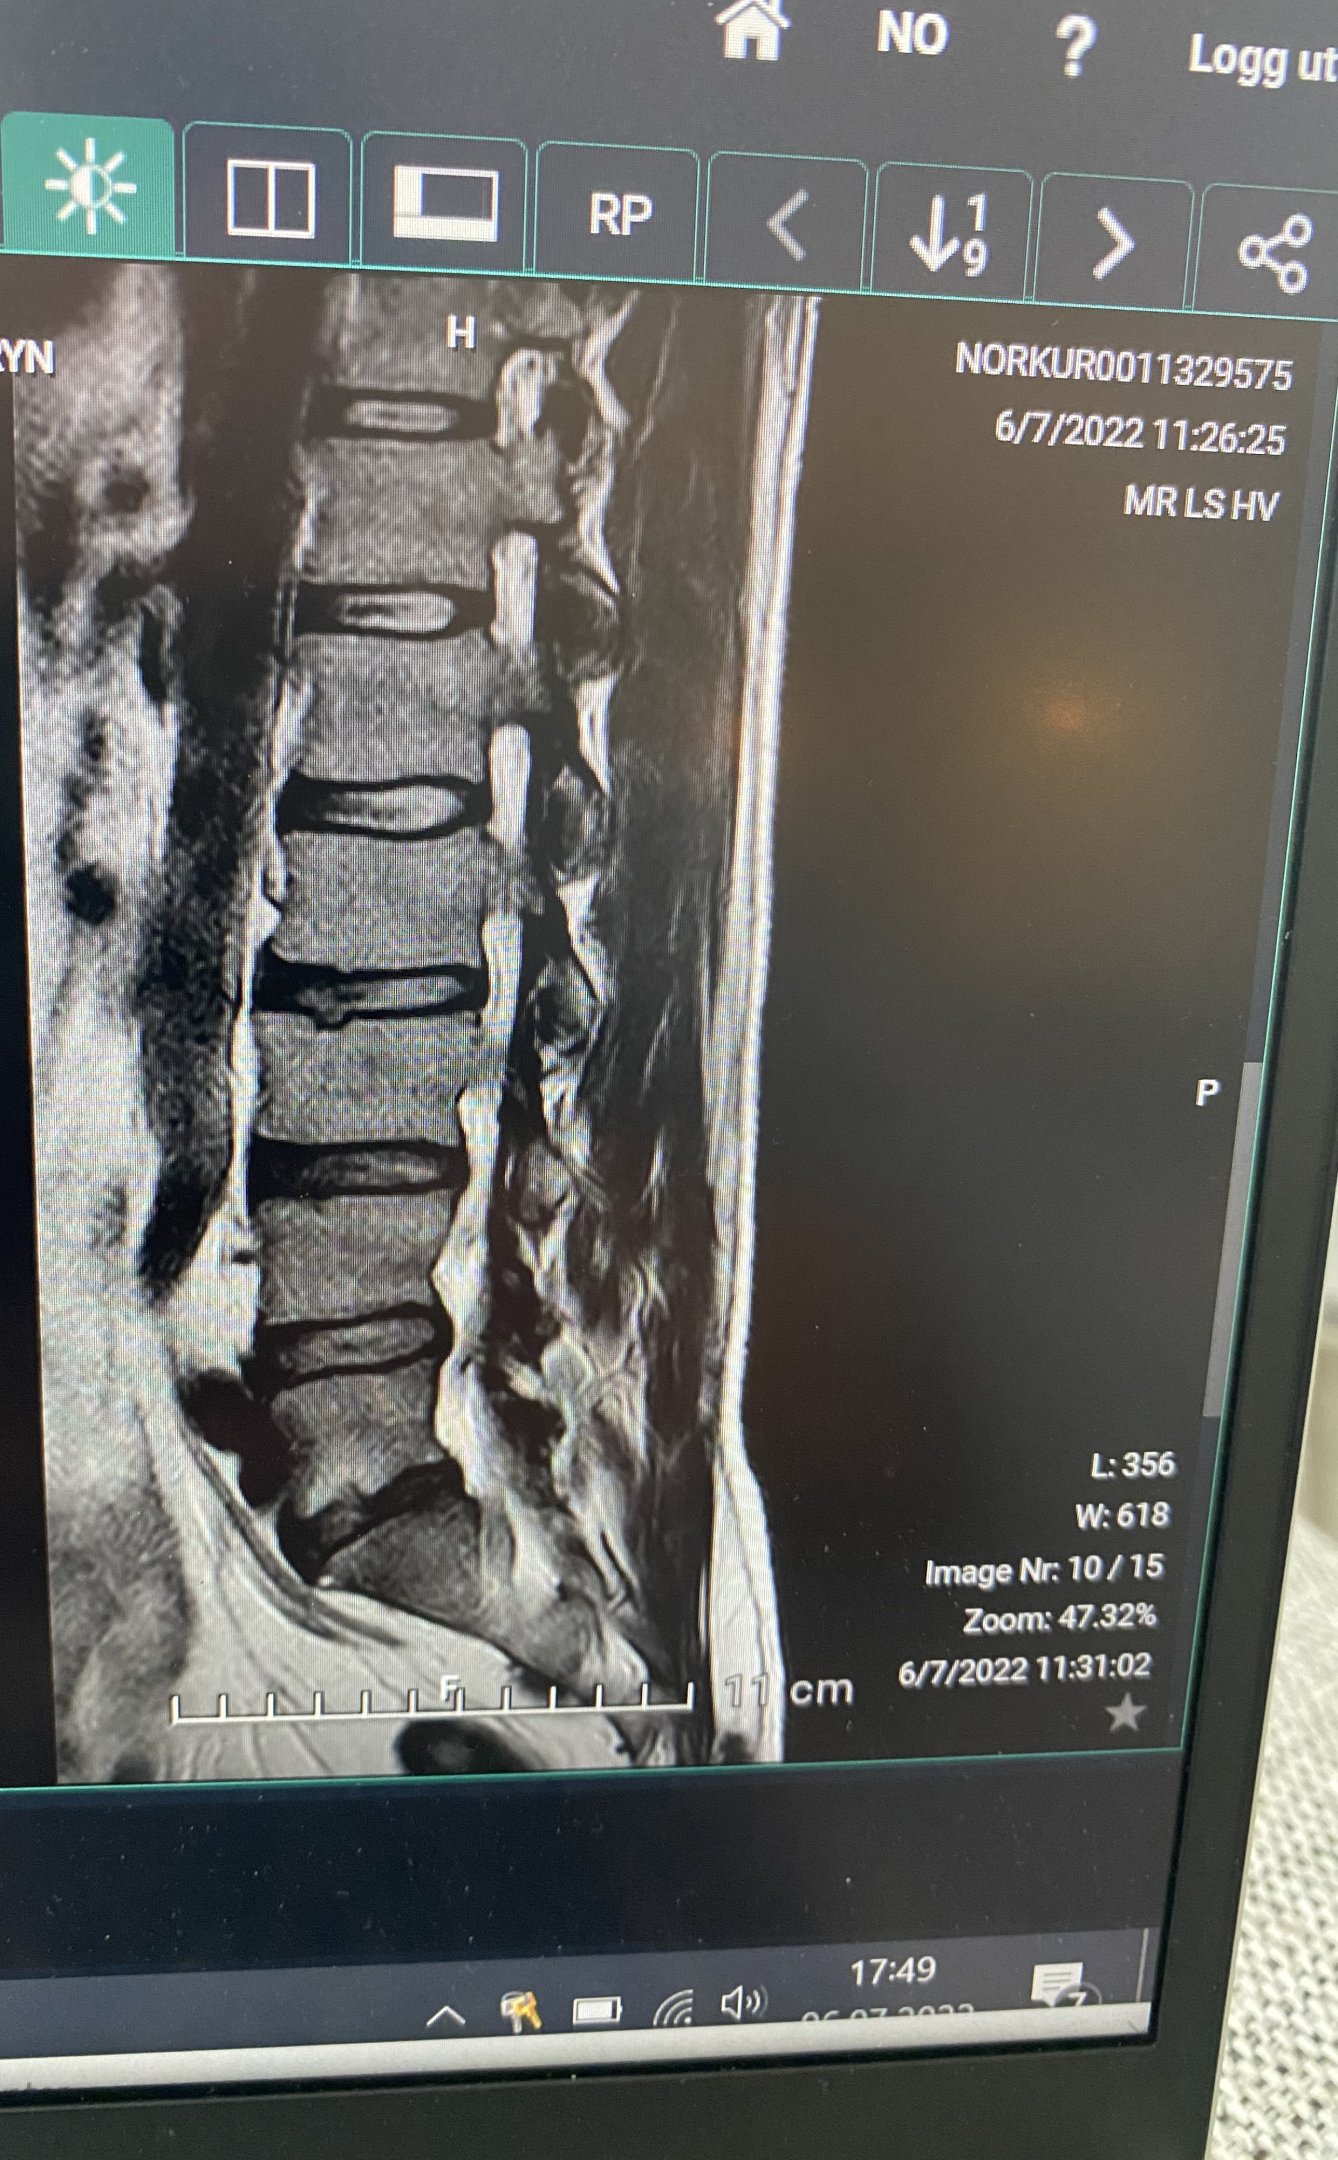

Skandinav Skrevet 6. juli 2022 Skrevet 6. juli 2022 Jeg ser kjøtt, ben, brusk, væske og skiveprolaps. 1

Lbeth Skrevet 6. juli 2022 Forfatter Skrevet 6. juli 2022 Skandinav skrev (2 minutter siden): Jeg ser kjøtt, ben, brusk, væske og skiveprolaps. Regner med det er en prolaps, men trodde det var enklere å se.. 😇

AnnonymG Skrevet 8. juli 2022 Skrevet 8. juli 2022 Når man skal tolke et MR-bilde er det helt relevant å forstå hvorfor bildet ble tatt i utgangspunktet. MR gir veldig mye informasjon, og MR-funn må korreleres med klinisk funn. I tillegg må man gjennomgå MR gjennom betydelig flere snitt enn det du viser her. Med mindre man har funnet akkurat det snittet som viser sykdomstegn, så er det nesten ikke mulig å konkludere på enkeltbilder uten å se dem i serier. Ikke en radiolog en gang kan trekke konklusjon fra de få snittene du har lagt ut. Man må nok vente på en beskrivelse fra kyndige, her er det allerede beskrevet engler og demoner, virker for meg som lite sannsynlig.... 😛